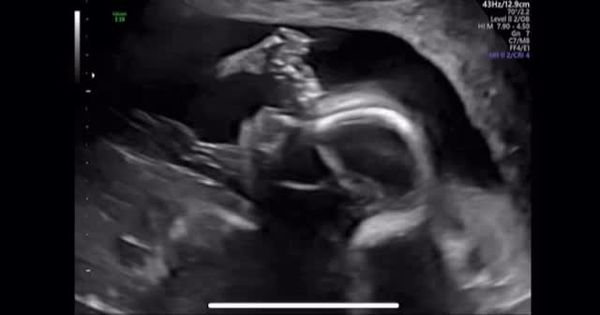

另外,林正姬也提到寶寶的胎名叫「BongBong」,並分享一段超音波的影片,可見寶寶在媽媽肚子裡十分活潑。事實上,林正姬與小6歲的芭蕾舞者金熙然(音譯)交往一年後,於2023年10月步入婚姻。金熙然曾是韓國國立芭蕾舞團的獨舞者,並曾在芭蕾經典《吉賽爾》中擔任主角,是一位備受肯定的專業舞者。

我會稍微讓大家看看他在媽媽肚子裡動著嘴巴的可愛模樣。